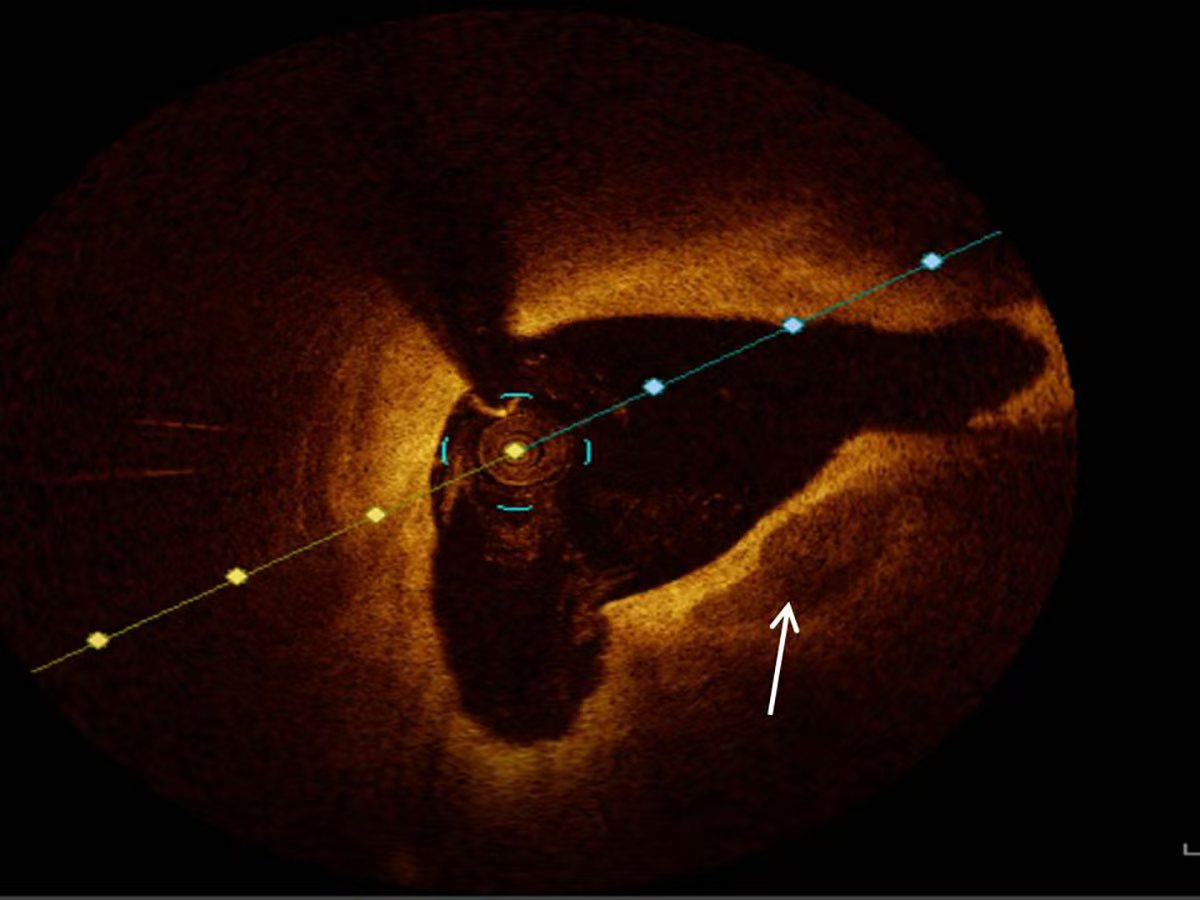

All patients diagnosed with ACS underwent OCT examinations utilizing the ILUMIEN OPTIS system (Abbott Vascular, Santa Clara, CA, USA) for imaging. The OCT data were interpreted and documented by two experienced interventional cardiologists who remained blinded to the clinical and laboratory data of the study population. In instances of disagreement regarding the interpretation of OCT images, resolution was achieved through consultation with an additional experienced interventional cardiologist. The characteristics of coronary artery plaques were documented in accordance with established guidelines derived from previous studies and consensus standards [13]. Calcified plaques presented as distinct areas characterized by well-defined borders, low attenuation, and heterogeneous low signal intensity [10, 13] (Fig. 1).

Fig. 1. Representative optical coherence tomography image of calcification (white arrow).